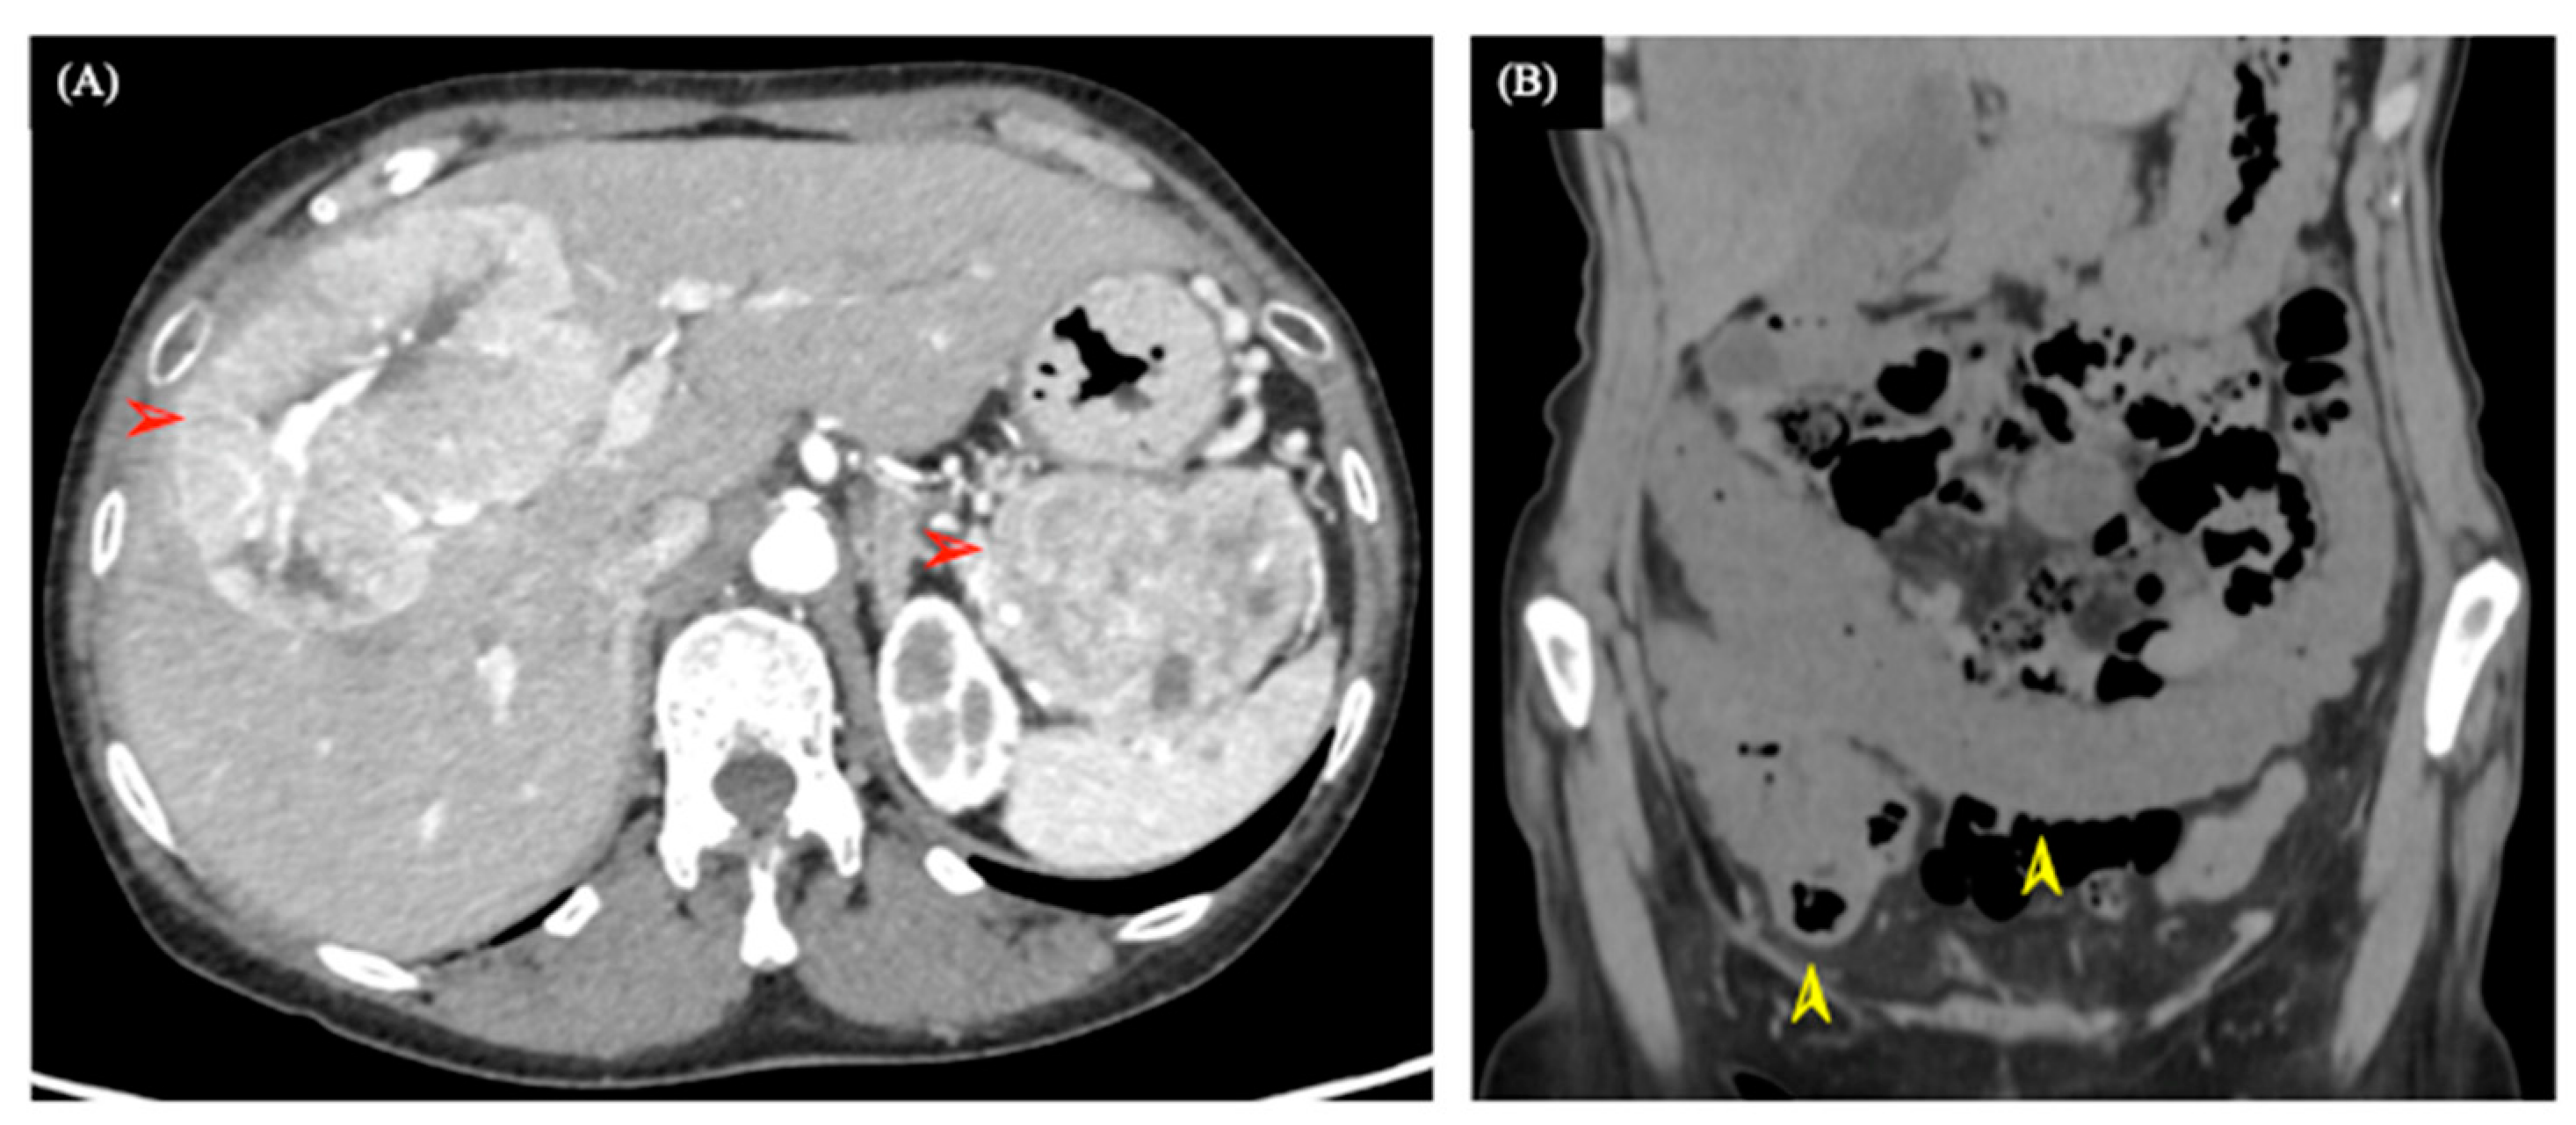

2. Case Presentation